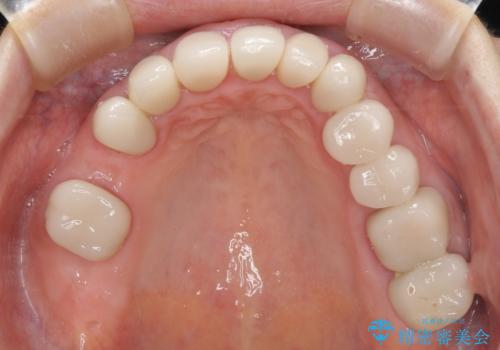

歯の欠損を放置 オールセラミックブリッジによる補綴治療

下顎には抜歯が必要な歯があったため、抜歯後に治癒を待ち、上顎とともにオールセラミックブリッジにて補綴治療を行うこととしました。

治療開始の日に欠損部も含めて仮歯が装着され、今までの不具合や不快感があっという間に改善されました。

抜歯部位の治癒を待つために時間がかかりましたが、来院回数は数回で済み、患者様には大変満足していただきました。